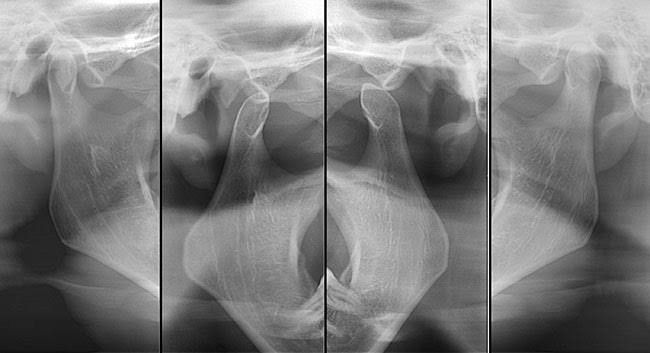

Radiografía A.T.M. digital

Técnica radiográfica que permite diagnosticar y tratar trastornos de la articulación temporomandibular.